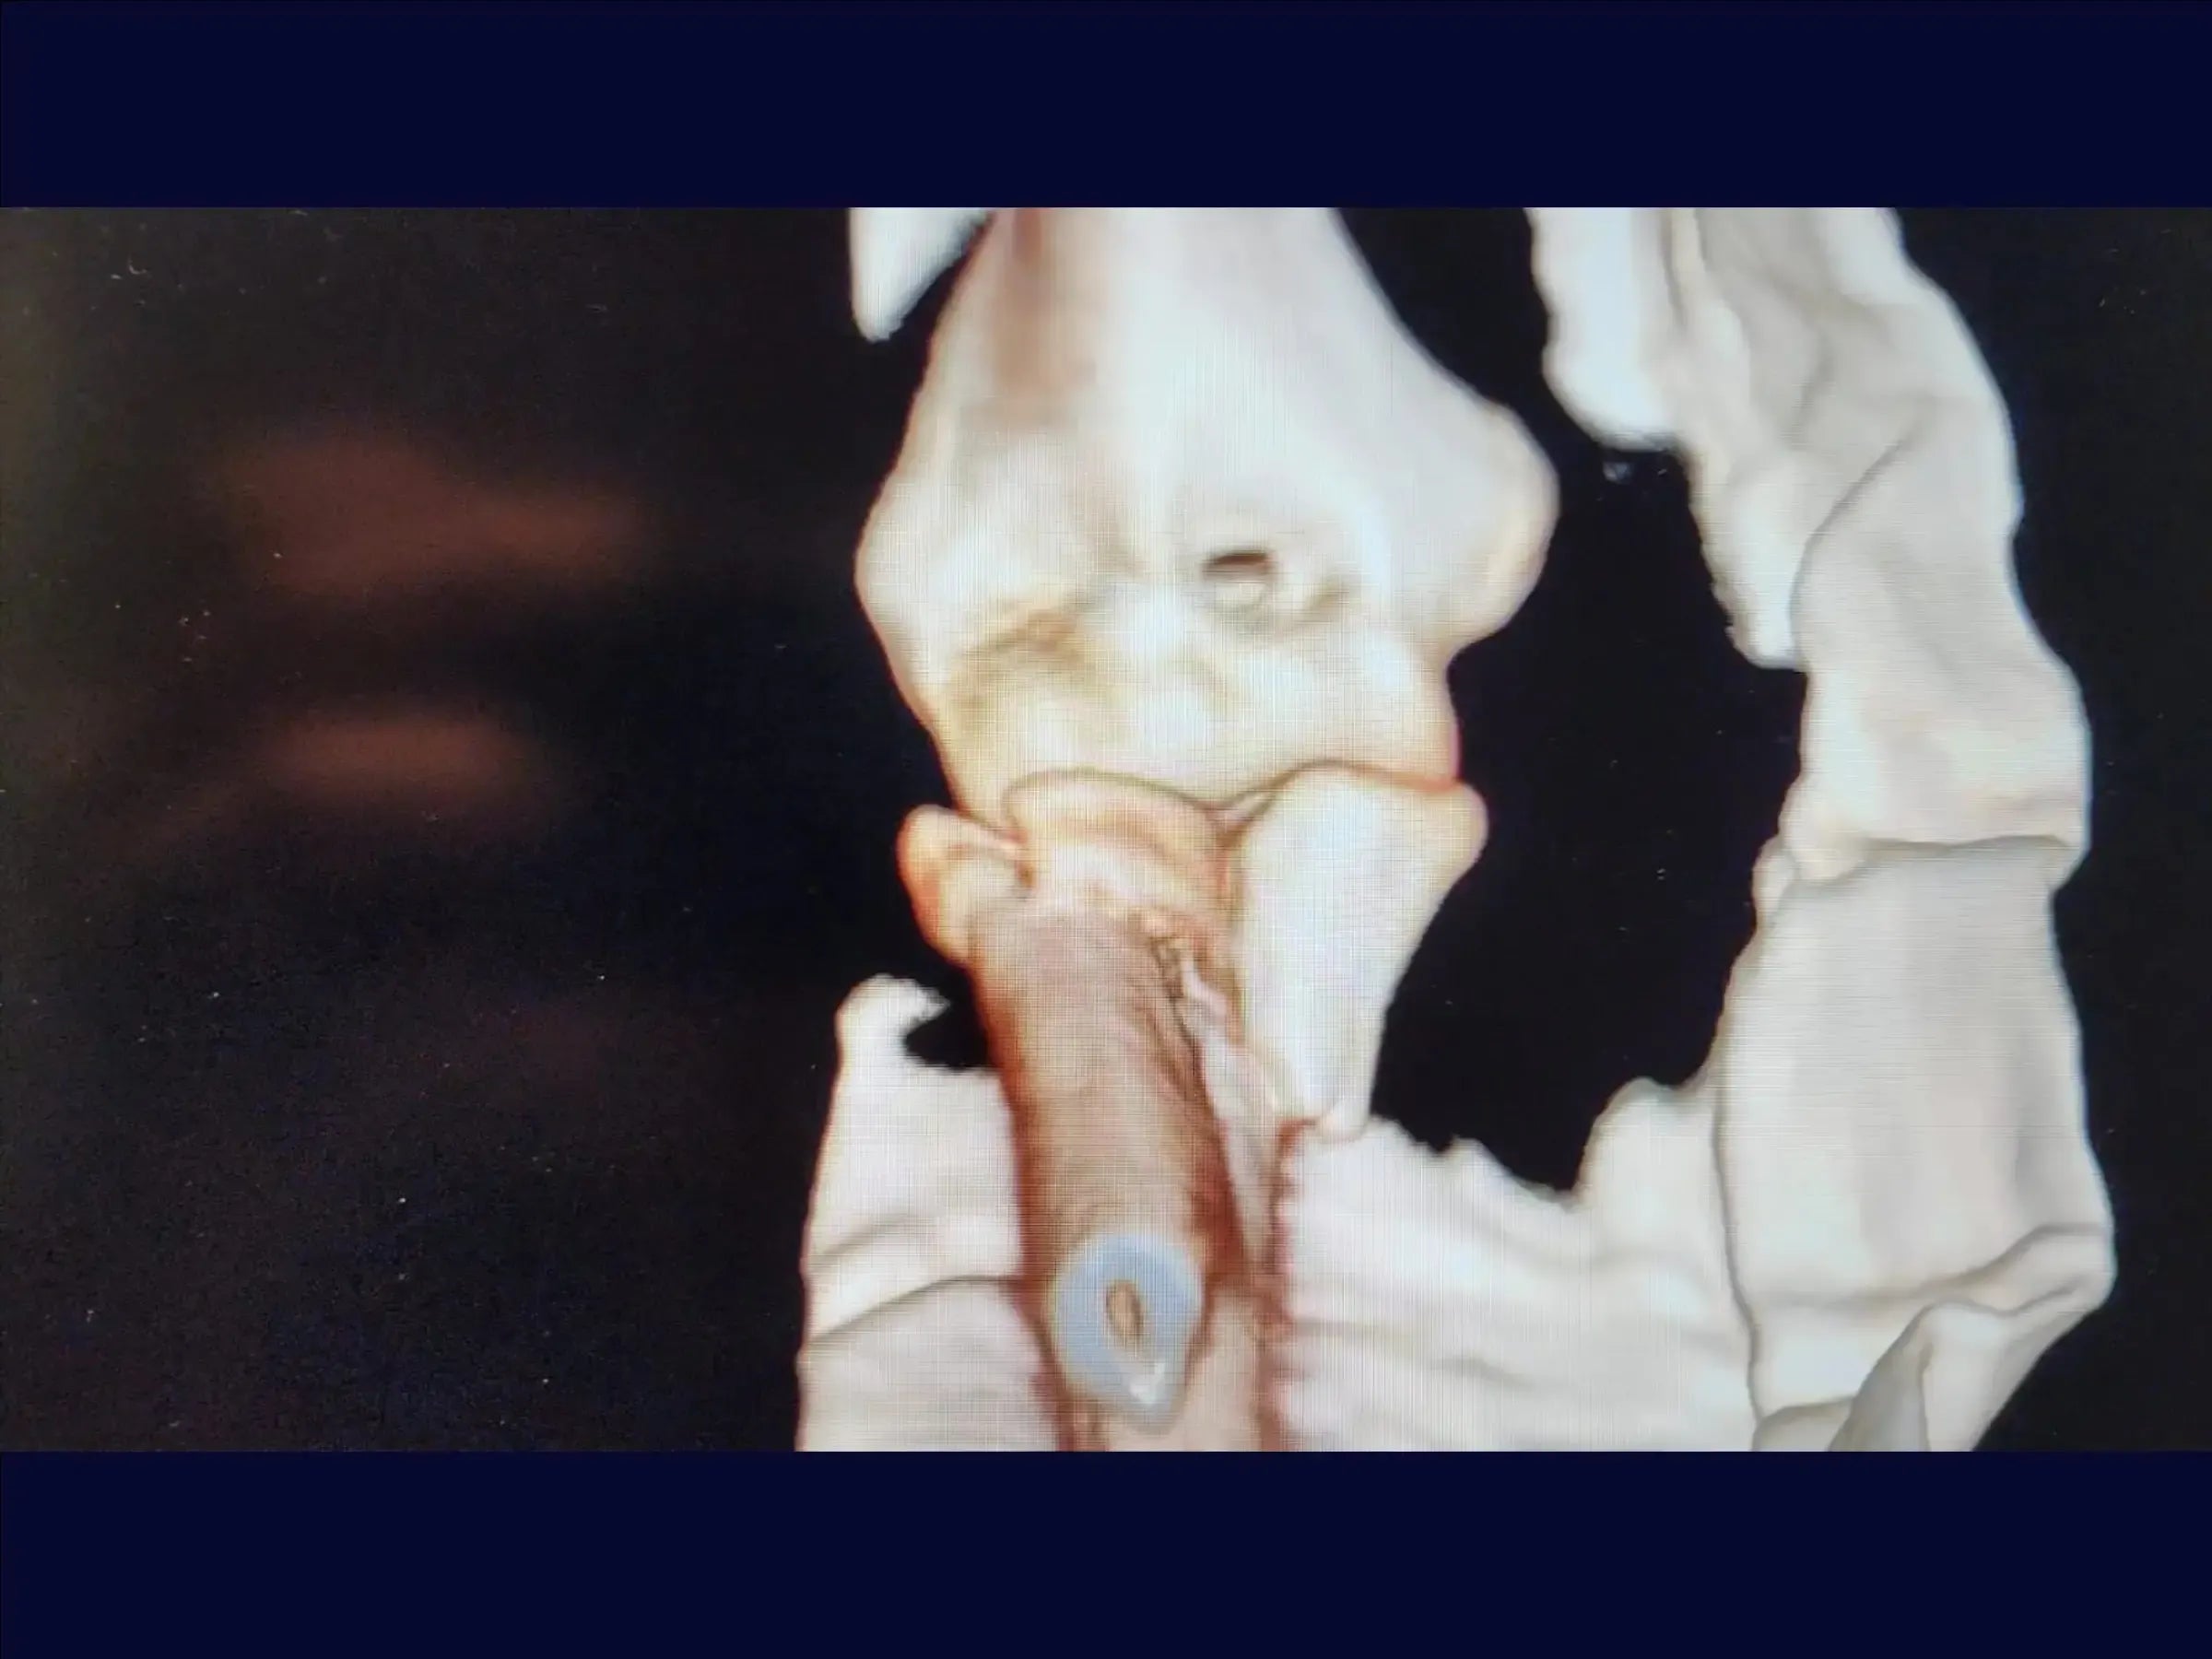

Fractura metafisaria del cúbito proximal con luxación y fractura de la cabeza radial (variante de Monteggia)

Mejore sus habilidades en el tratamiento de una de las lesiones de codo más complejas: la fractura metafisaria del cúbito proximal asociada a la luxación posterior y la fractura de la cabeza radial, conocida como variante de Monteggia . Esta formación abarca la reducción anatómica del cúbito y la cabeza radial, la fijación con placas y tornillos, y la reinserción de estructuras ligamentosas, con el objetivo de restaurar la estabilidad articular y permitir la movilidad temprana del codo, minimizando el traumatismo tisular y optimizando el resultado estético.

- Tratamiento quirúrgico de la fractura metafisaria del cúbito proximal con luxación posterior y fractura de la cabeza radial ( variante de Monteggia ).

- Reducción anatómica del cúbito y la cabeza radial.

- Fijación de la cabeza radial : Reducción manual con tornillos minifragmentarios en técnica de trípode con estabilidad subcondral .

- Reinserción de ligamentos : Anclaje metálico de 5,0 mm para una reinserción precisa de las estructuras laterales, garantizando la estabilidad de la articulación.